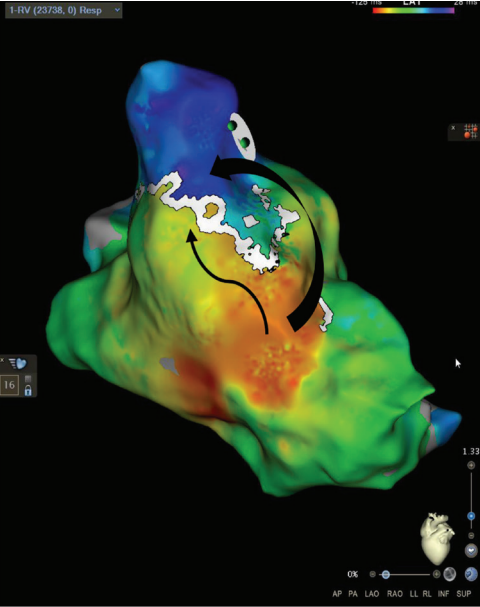

Wavefront Discontinuity Lines

The RV pacing map set was again used in a local activation time format to evaluate wavefront discontinuity lines (WADL). This recently described method of functional mapping developed by Maher et al6 uses the mapping system to automatically identify areas of slow activation and fixed lines of block to target for ablation. To visualize the lines of discontinuity, we titrated the early-meets-late setting between 25% to 35% of the mapped cycle length in the ventricle. This is visualized in Figure 3 by a white line in the same area of RVOT with activation meeting a line of block within the surgical scar emphasized by the black arrows. The WADL in this map again correlated with the same area marked as a SCAI and ILAM deceleration zone. To the author’s knowledge, there are no prior published reports of using WADL mapping in repaired TOF.

Activation and Entrainment

After examining the baseline voltage to identify surgical scar, SCAIs and functional substrate maps, a pacing catheter was then placed in the predicted VT isthmus (yellow circle, Figure 1). VT was easily induced with 2 extrastimuli off of isoproterenol. A single monomorphic tachycardia at a cycle length of 270 ms was induced originating from the RV (Figure 4A). Entrainment was performed from the catheter that was preemptively put into the isthmus at a cycle length of 250 ms, which successfully entrained the tachycardia. The post-pacing interval - tachycardia cycle length from this location was 38 ms with a small degree of manifest fusion and a stim to QRS that was extremely short (Figure 4B). We believe these findings were all consistent with the area of entrainment being in very close proximity to the exit of the tachycardia. An attempt at VT activation mapping was performed with the Optrell (Figure 5); however, this tachycardia was extremely poorly tolerated. Ablation was performed across this isthmus and within the scar followed by high-output pacing to confirm noncapture of ablated tissue. A ventricular stimulation protocol was performed with up to 3 extrastimuli from 2 locations in the RV on and off isoproterenol with noninducibility of ventricular tachyarrhythmias. At 7-month follow-up, the patient had no further VT on the same dose of dofetilide that he was previously on for atrial tachyarrhythmias.